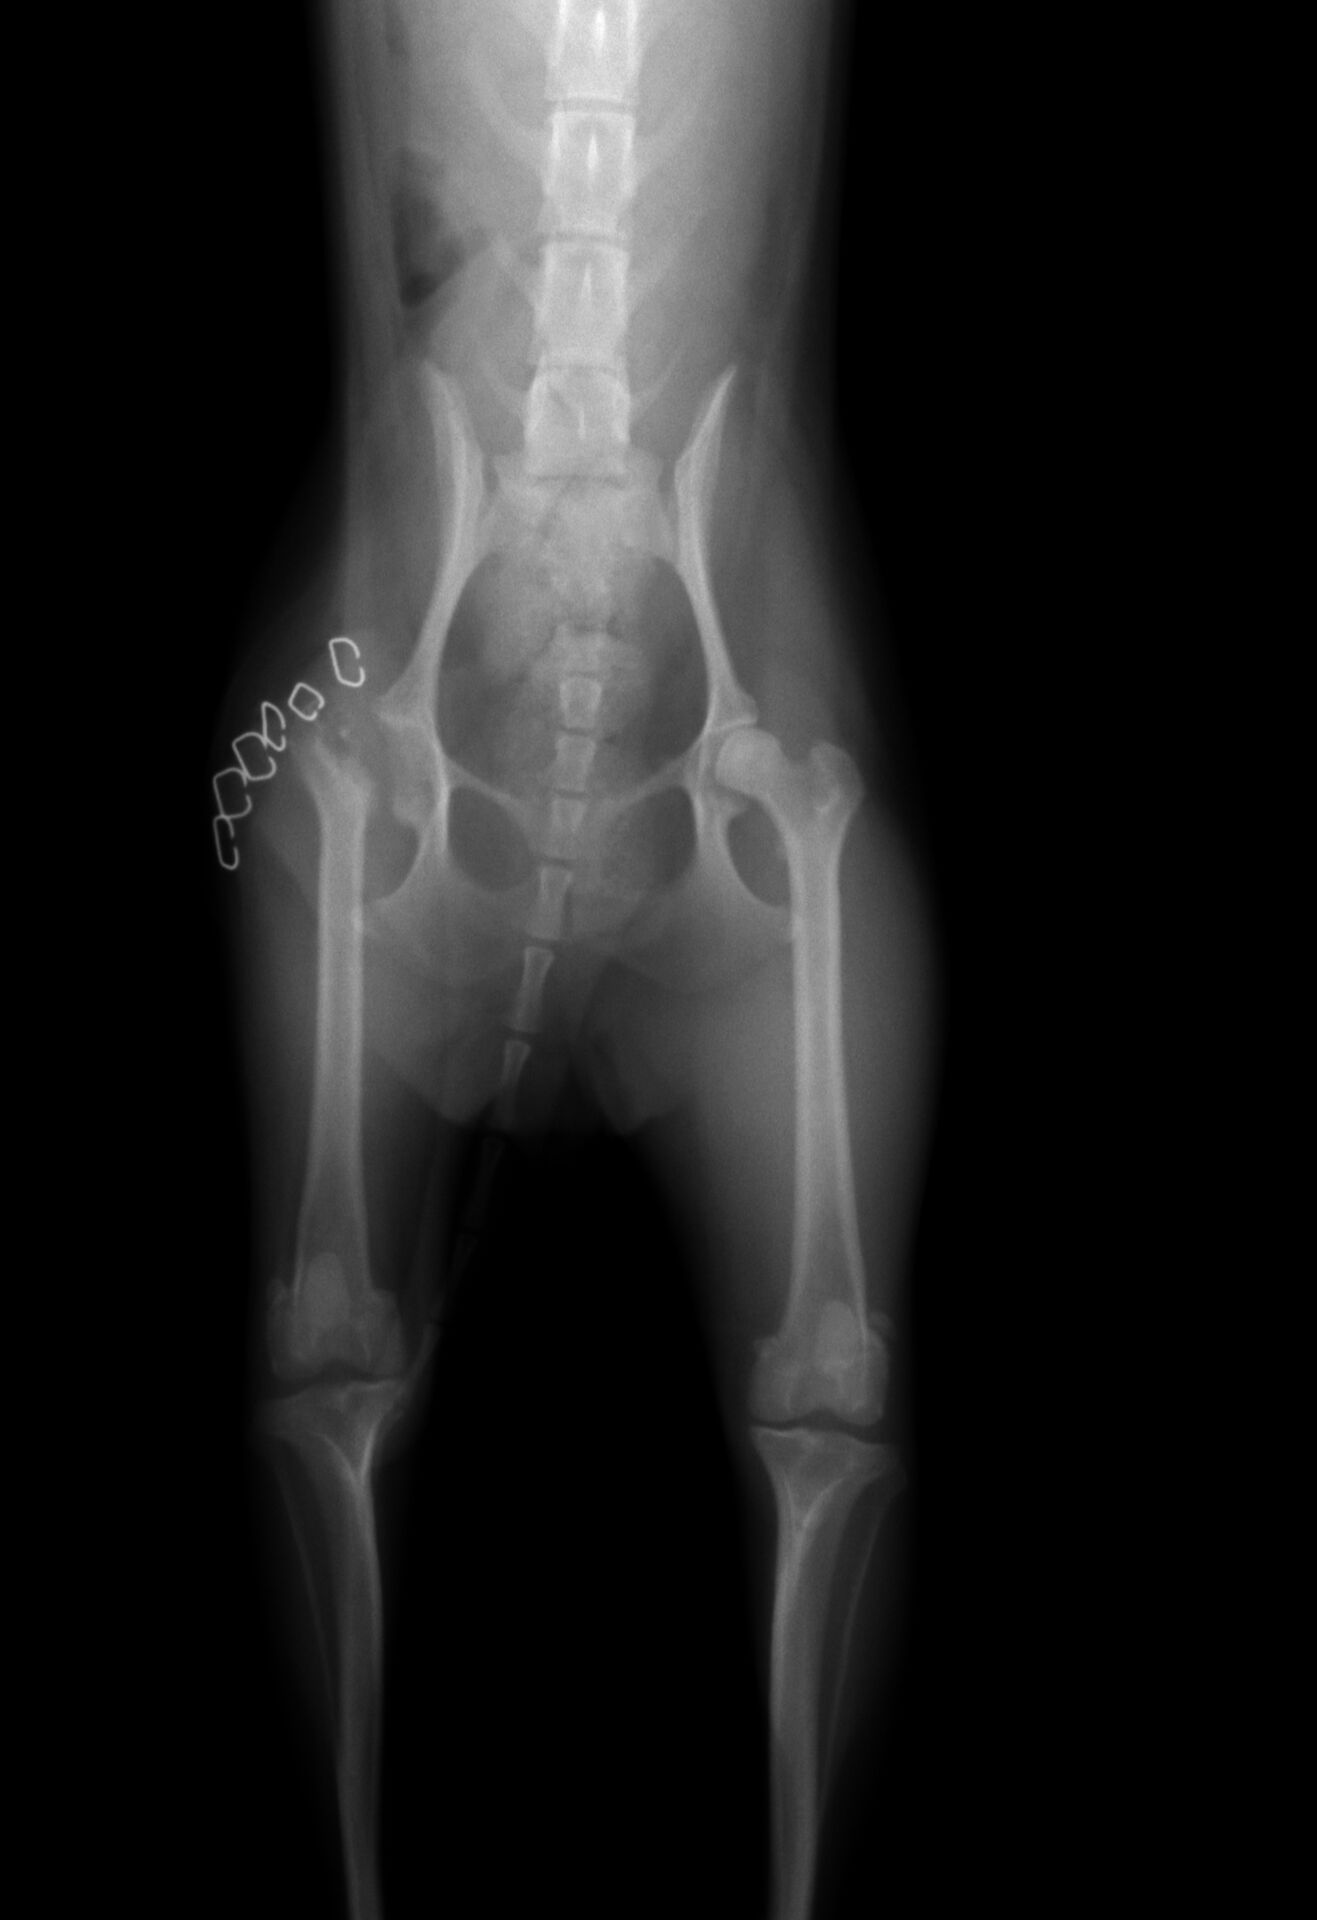

症例は、1才のトイ・プードルの女の子です。右の後ろ脚を挙げて歩くことが

多くなったとのことで来院されました。触診で右後ろ脚を後ろに伸展すると

かなり痛がったので、股関節に痛みがあると判断しレントゲンを撮りました。

その結果が下の写真です。

わかりにくいのですが、左の写真 中央部に股関節(骨盤と大腿骨が接している

部分の関節)に隙間 (黄色矢印) があります。普通はもっと狭いのですが、症例はかなり広く

なっています。この画像からレッグペルテスと判断しました。この関節は放っておくと

どんどんひどくなり、患肢を使わなくなっていきます。現に右の写真で、右脚の大腿部の

筋肉が細くなっています(黄色矢印)ので、あまりこの脚をあまり使っていないため

筋肉が萎縮し始めています。治療が遅れると、治療後も脚を使わなくなってしまうことが

あります。